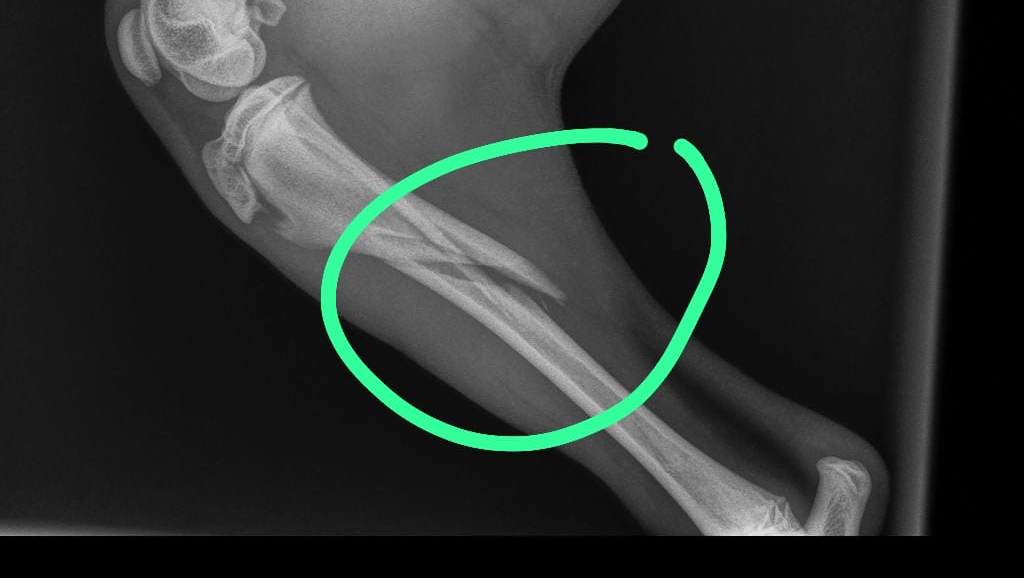

Wie zou me kunnen helpen me lieve meissie te kunnen helpen met de kosten achter poot gebroken en ik hoop dat hier mensen zijn die me kunnen helpen zal ik erg waarderen en dat ze snel weer opknapt mijn lieve Bintang

Help operatie kosten